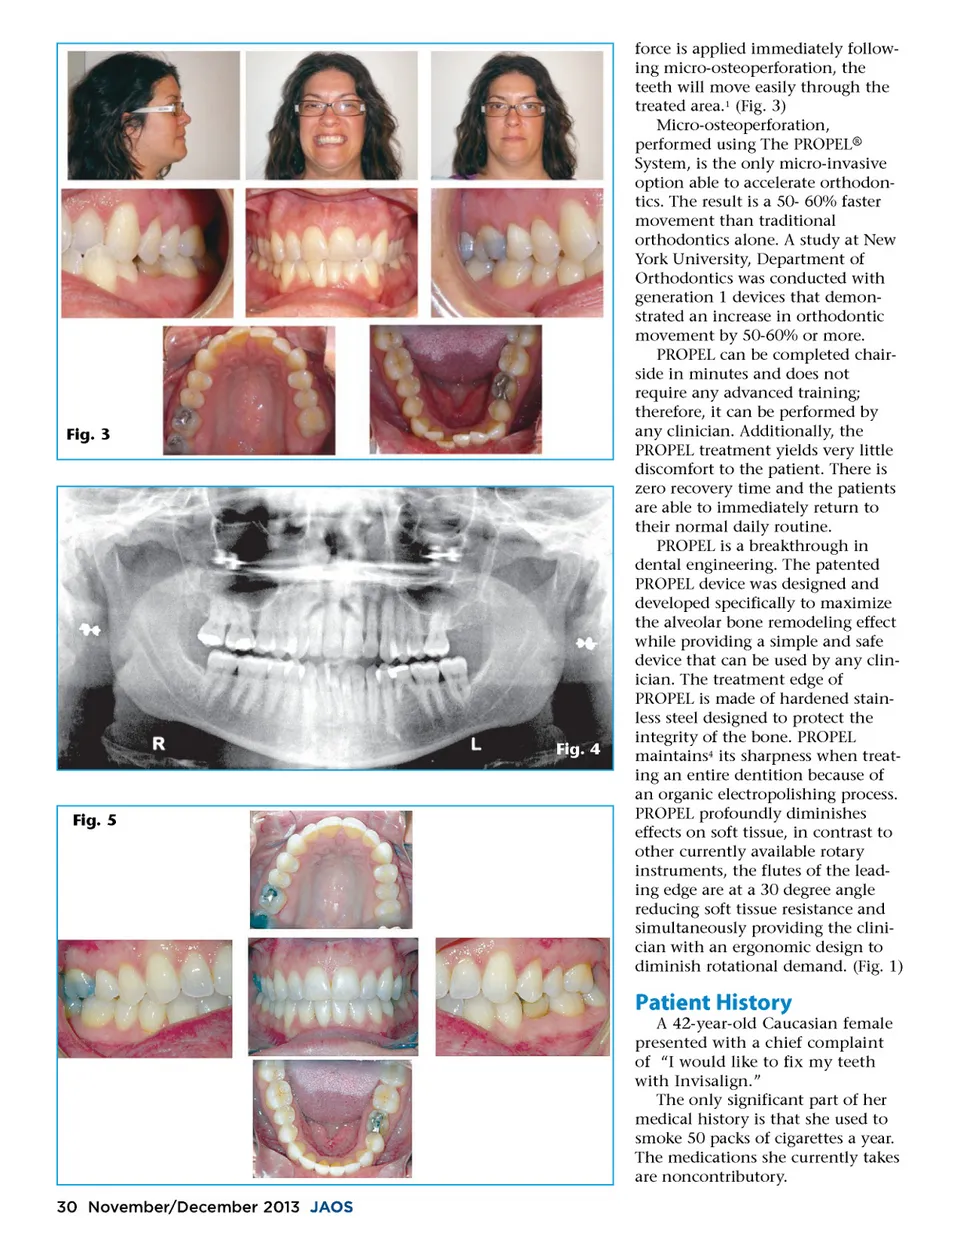

Fig. 3 Fig. 4 Fig. 5 force is applied immediately follow-ing micro-osteoperforation, the teeth will move easily through the treated area. 1 (Fig. 3) Micro-osteoperforation, performed using The PROPEL ® System, is the only micro-invasive option able to accelerate orthodon-tics. The result is a 50-60% faster movement than traditional orthodontics alone. A study at New York University, Department of Orthodontics was conducted with generation 1 devices that demon-strated an increase in orthodontic movement by 50-60% or more. PROPEL can be completed chair-side in minutes and does not require any advanced training; therefore, it can be performed by any clinician. Additionally, the PROPEL treatment yields very little discomfort to the patient. There is zero recovery time and the patients are able to immediately return to their normal daily routine. PROPEL is a breakthrough in dental engineering. The patented PROPEL device was designed and developed specifically to maximize the alveolar bone remodeling effect while providing a simple and safe device that can be used by any clin-ician. The treatment edge of PROPEL is made of hardened stain-less steel designed to protect the integrity of the bone. PROPEL maintains 4 its sharpness when treat-ing an entire dentition because of an organic electropolishing process. PROPEL profoundly diminishes effects on soft tissue, in contrast to other currently available rotary instruments, the flutes of the lead-ing edge are at a 30 degree angle reducing soft tissue resistance and simultaneously providing the clini-cian with an ergonomic design to diminish rotational demand. (Fig. 1) Patient History A 42-year-old Caucasian female presented with a chief complaint of “I would like to fix my teeth with Invisalign.” The only significant part of her medical history is that she used to smoke 50 packs of cigarettes a year. The medications she currently takes are noncontributory. 30 November/December 2013 JAOS